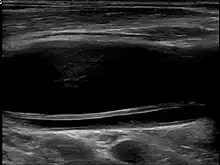

Dissection in ultrasound